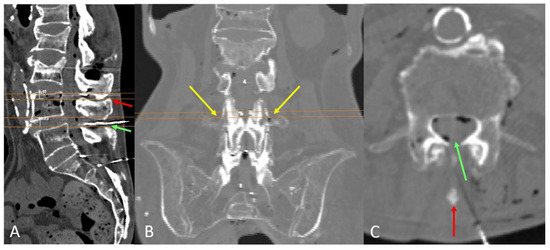

Open AccessArticle

by

Anna Puigdellívol-Sánchez, Hipólito Labandeyra, Alberto Prats-Galino and Xavier Sala-Blanch

NeuroSci 2025, 6(4), 119; https://doi.org/10.3390/neurosci6040119 - 21 Nov 2025

Background: The skin-to-transverse process distance (st) correlates with the skin-to-dural sac depth (d) and may be used to estimate optimal angles for perpendicular needle insertion using the formula inverse cosine d/√(1 + d2), as outlined in free visual guides. Objective: We

Background: The skin-to-transverse process distance (st) correlates with the skin-to-dural sac depth (d) and may be used to estimate optimal angles for perpendicular needle insertion using the formula inverse cosine d/√(1 + d2), as outlined in free visual guides. Objective: We aimed to analyze the relationship between the transverse process and dural sac depth at lumbar levels relevant to spinal anesthesia and to determine the range of planes where perpendicular paramedian needle insertion is feasible when midline access is not viable. Methods: Ten ex vivo trunks were flexed using an abdominal support, and CT scans were performed. Correlations between the transverse process and dural sac depth were evaluated from L3 to S1. Perpendicular planes at the level of needle paths were examined at L3–L4 and L4–L5. Median path viability was assessed. Results: The transverse process aligned with the dorsal dural sac at L3, the posterior third at L4, and the middle zone at L5 or S1. Median needle insertion was not viable in 20–30% of L4–L5 and L3–L4 levels, respectively. However, paramedian access was possible. The vertical range of viable paramedian planes was 8.7 ± 2.9 mm (L4–L5) and 7.9 ± 1.9 mm (L3–L4). Coronal reconstructions showed that the upper level of the transverse process correlates with the skin-perpendicular planes where insertion is likely to succeed. Conclusion: Many elderly spines lack viable midline paths. The superior aspect of the transverse process serves as a useful landmark for estimating dural sac depth, calculating paramedian angles, and identifying the plane for successful perpendicular needle insertion.

Figure 1